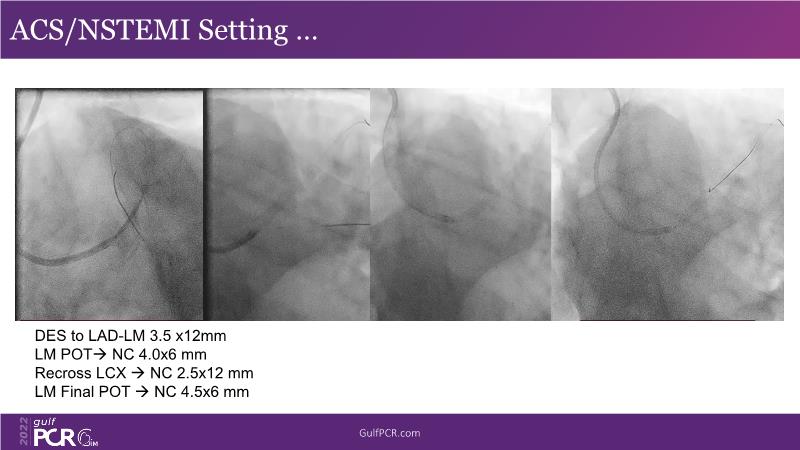

Optimal PCI in patient with long calcified lesion

In this session, follow a LIVE case from the Chest Diseases Hospital in Kuwait and learn what the best strategy is to treat patients who present with a very long calcified coronary artery lesion, as well as how to select the best device and which different types of stents can be used.

- To learn correct interpretation of a long-calcified lesion and how to adopt procedural strategy

- To know the impact of DES platform in the management of a complex patient